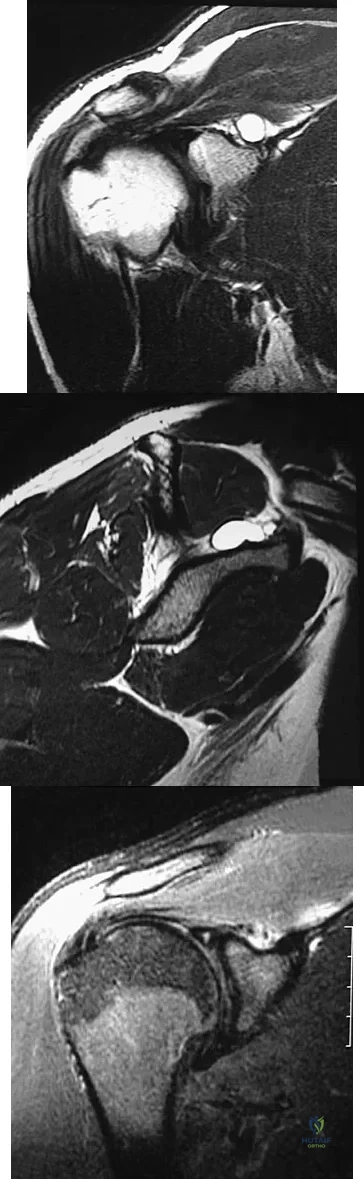

A 51-year-old male truck driver has had progressive left hip pain for more than 2 years, and he reports that the pain has become severe in the past 9 months. He is now unable to work because of the pain. Examination reveals that range of motion of the hip is limited to 95 degrees of flexion, 0 degrees of internal rotation, and 20 degrees of external rotation. The plain radiograph, MRI scan, and intraoperative gross photographs are shown in Figures 9a through 9d. Management should consist of

Explanation:

The diagnosis is synovial chondromatosis. While the plain radiograph fails to show any calcifications, the MRI scan shows an intra-articular mass that involves the capsule. Grossly multiple granular cartilage nodules are seen. Management should consist of removing all loose bodies along with the synovial membrane.